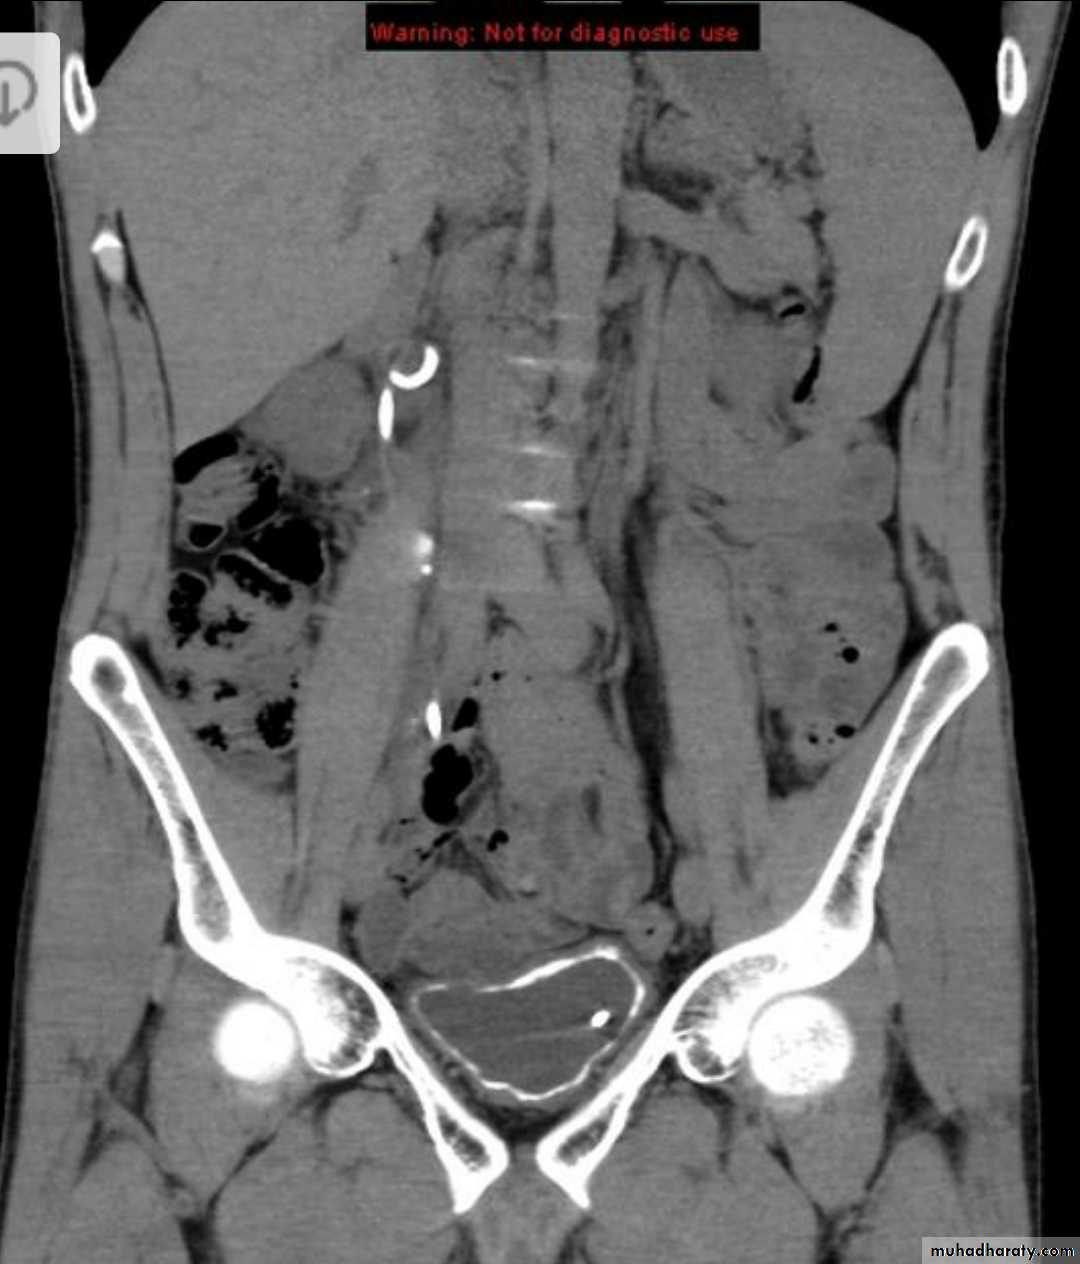

CT scanstones in kidneys